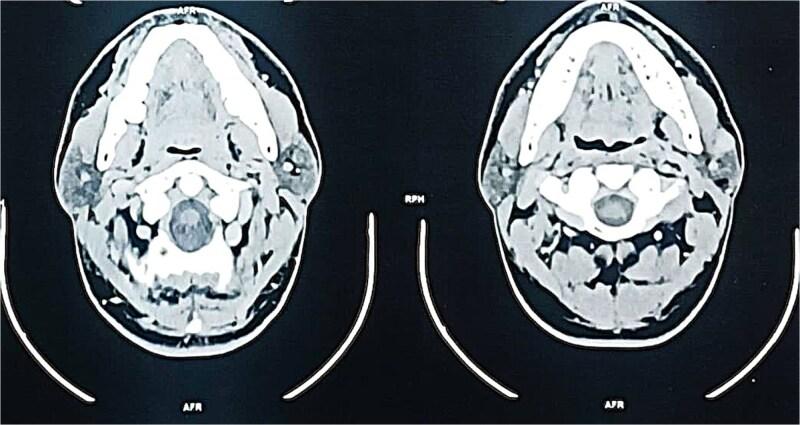

Sebaceous lymphadenoma is a rare benign tumor of the salivary glands, with fewer than 50 cases reported worldwide. Its clinical and radiological resemblance to malignant tumors poses diagnostic challenges. A 35-year-old female presented with a slow-growing, painless left parotid mass persisting for 2 years. Ultrasonography revealed a well-circumscribed, hypoechoic nodule measuring 2.5 cm. Fine-needle aspiration cytology suggested a benign lymphoid lesion, but definitive diagnosis required histopathological examination post-superficial parotidectomy. Microscopic analysis showed proliferating sebaceous cells within lymphoid stroma, confirmed by immunohistochemistry (EMA+, CK7-). No recurrence was observed at 12-month follow-up. This case underscores the importance of histopathology in distinguishing sebaceous lymphadenoma from carcinomas (e.g. sebaceous carcinoma) or Warthin tumor, particularly in regions with limited molecular diagnostic resources. Despite its rarity, sebaceous lymphadenoma should be considered in differential diagnoses of parotid masses to avoid unnecessary aggressive treatments.